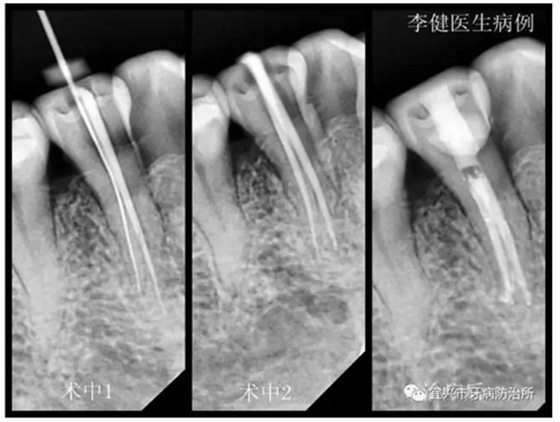

患者,女,55歲,右下前磨牙繼發(fā)齲伴自發(fā)性疼痛前來(lái)就診,X線片顯示為雙根管。術(shù)中1選用鎳鈦根管預(yù)備銼第一次根管預(yù)備未找到,后選用8號(hào)細(xì)銼在根中1/3處找到另一根管,拍X線片確認(rèn)。術(shù)中2再次用鎳鈦根管銼預(yù)備,并用次氯酸鈉溶液反復(fù)沖洗根管。最后利用超聲振蕩機(jī)蕩洗根管后,用熱牙膠系統(tǒng)嚴(yán)密充填根管,并用樹脂充填窩洞。待后期烤瓷冠修復(fù)。